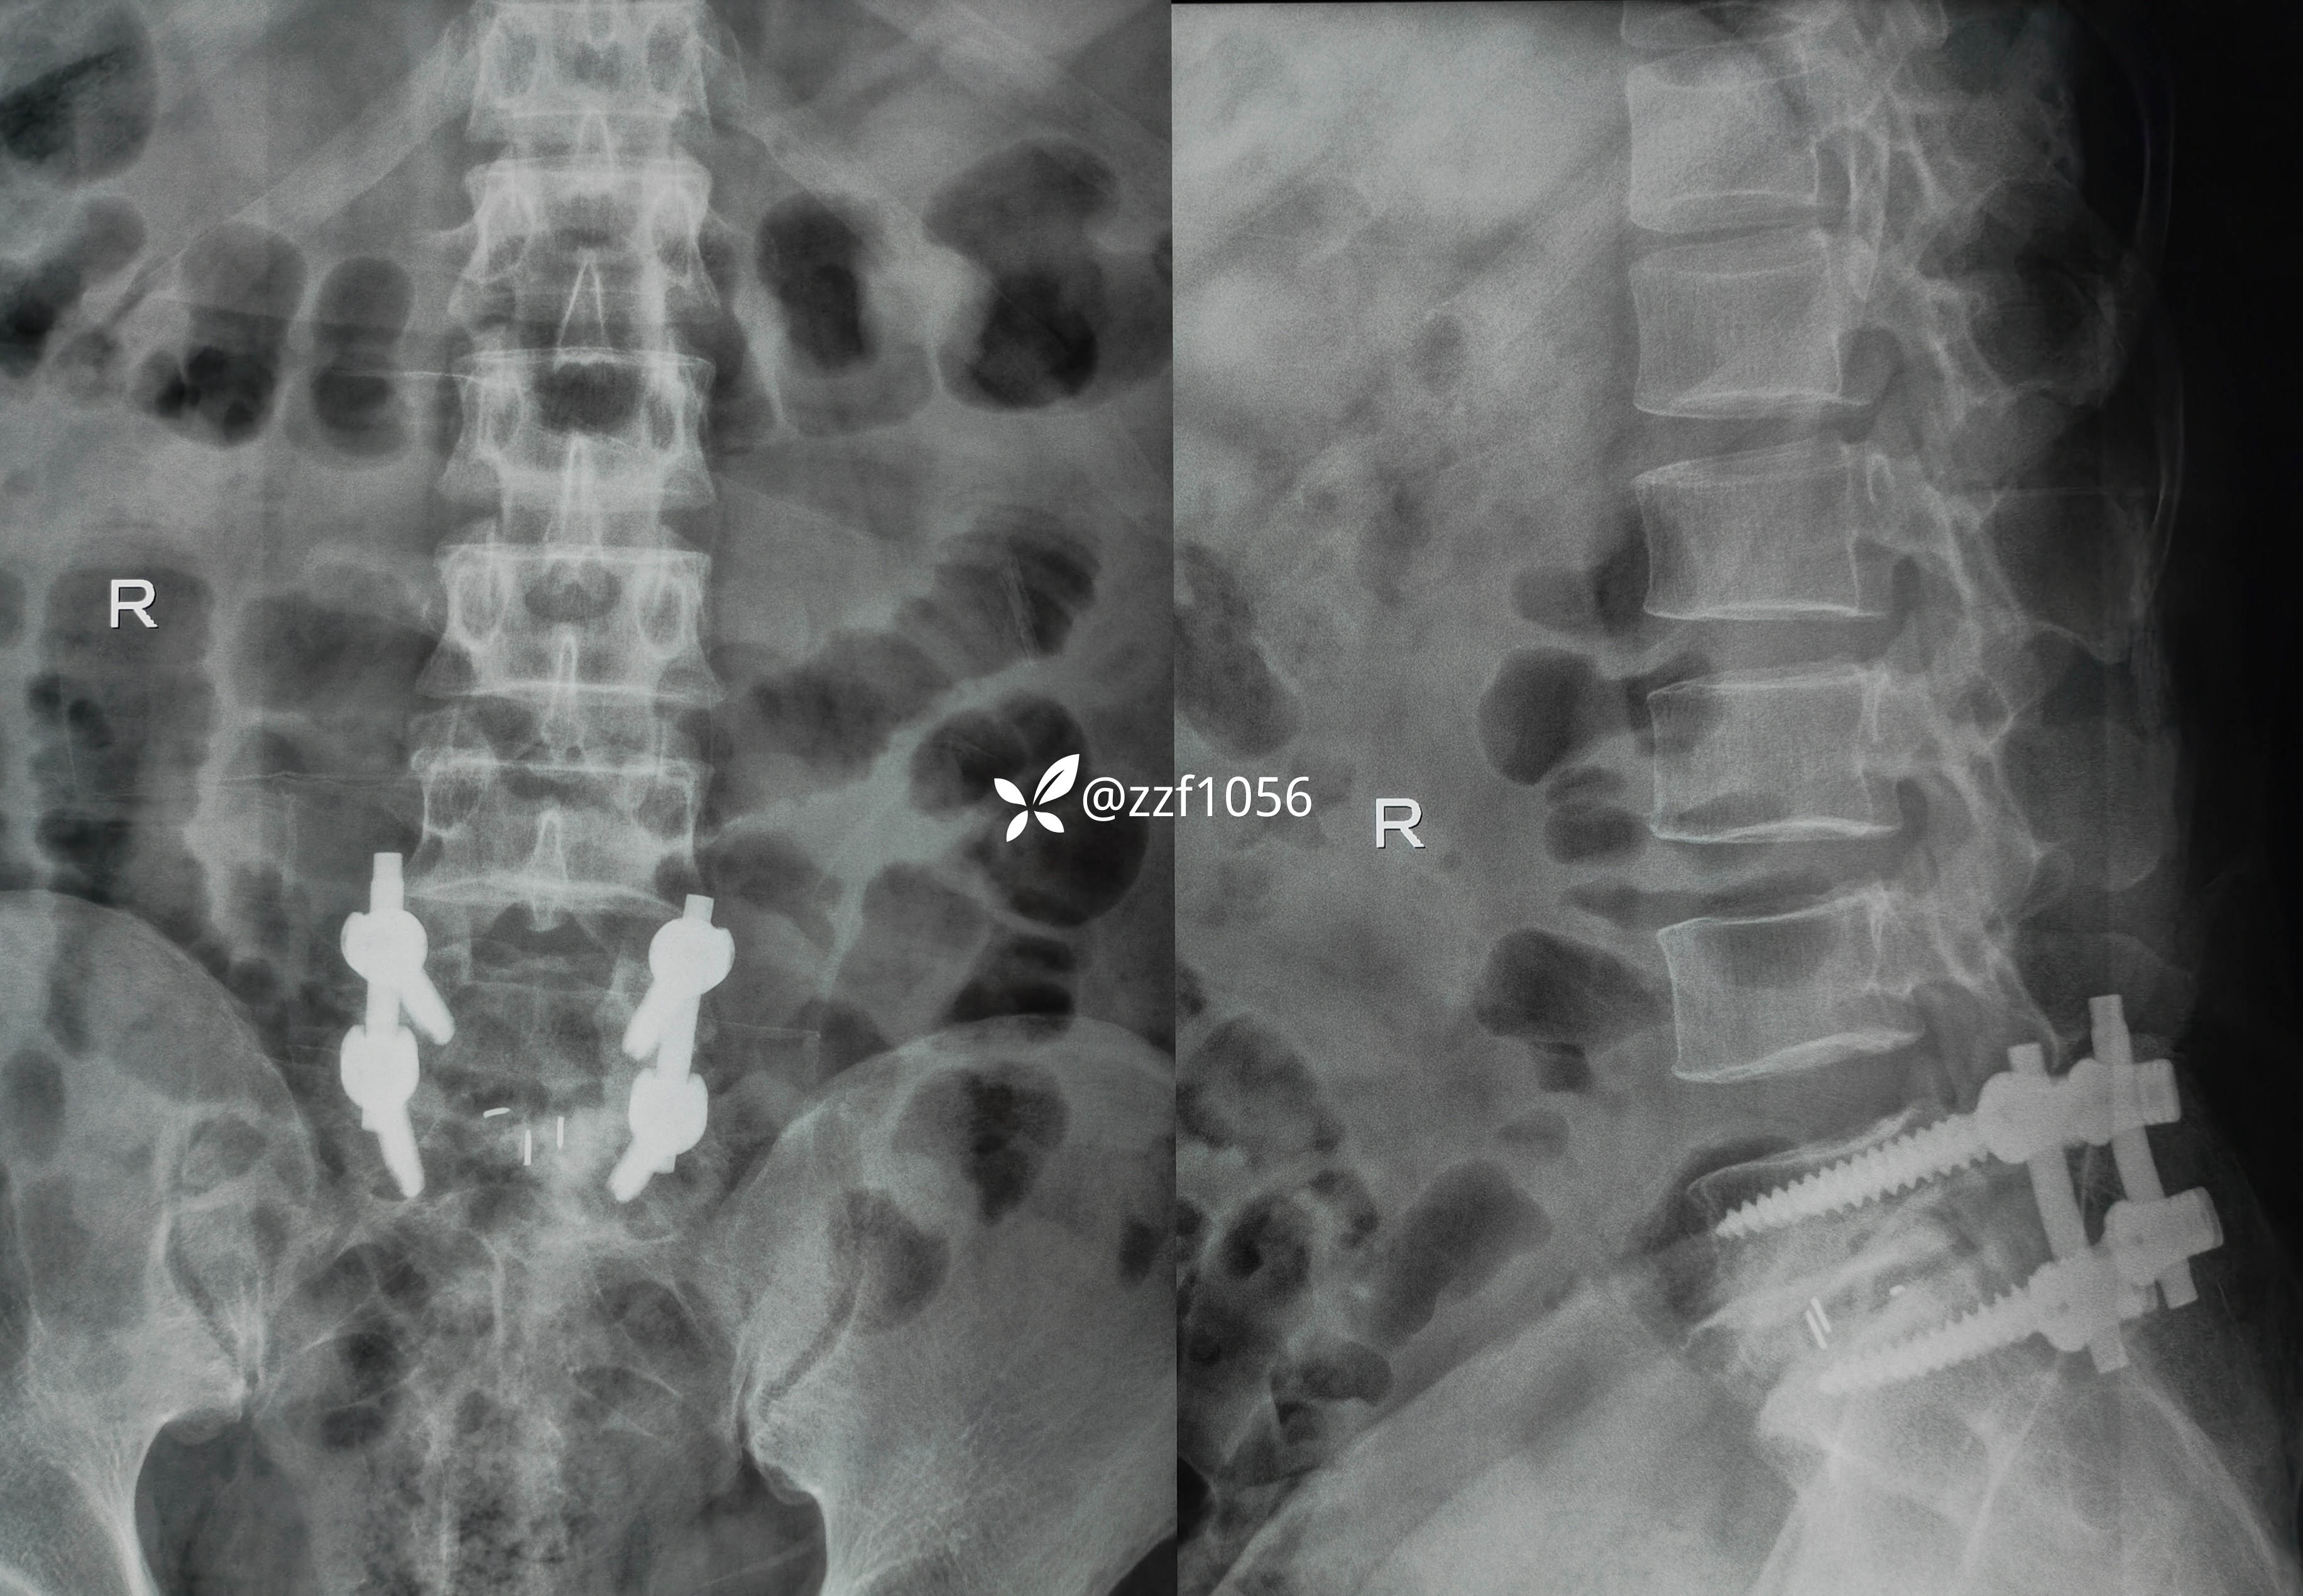

右侧减压彻底,L5S1根松弛,保留了左侧关节突所以撑开有限,使用8mmCage

目前患者已拆线,腰封保护下下床行走可,疼痛症状消失,右足麻木稍改善,肌力仍3级群,继续康复。